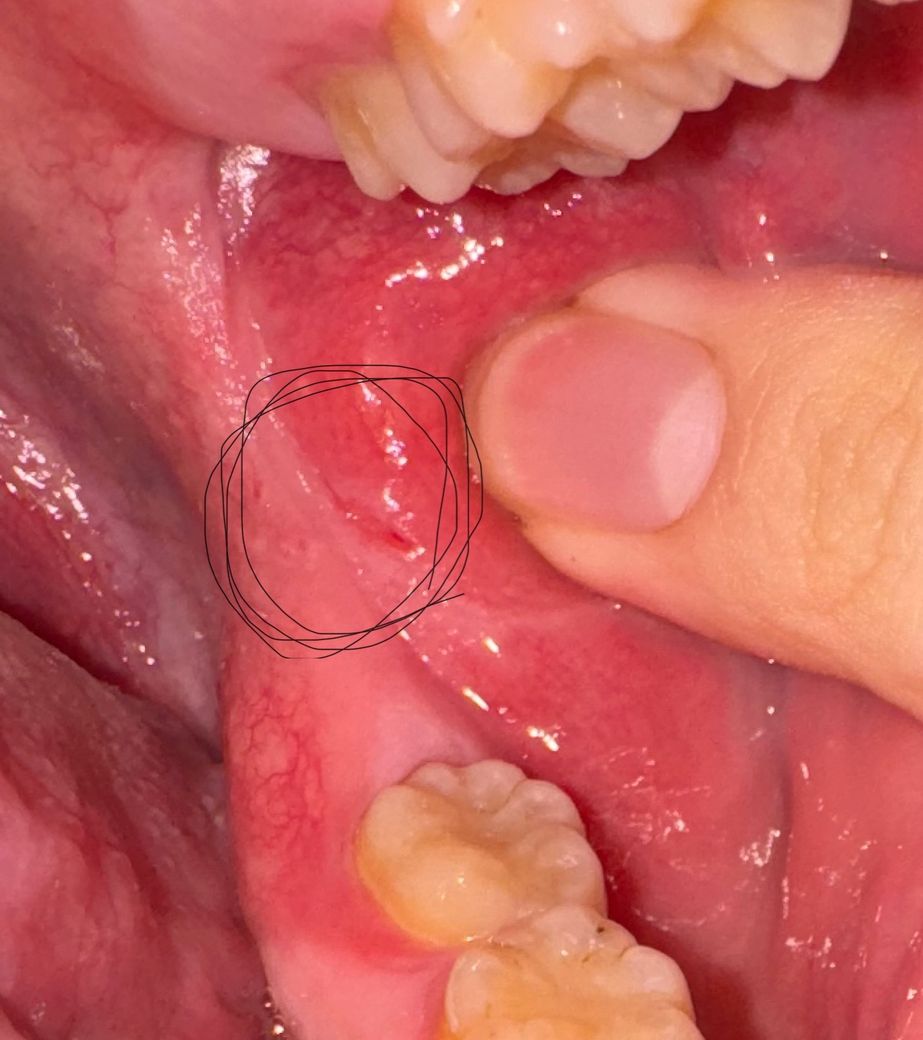

구강 볼점막에 상처가 난건가요 아니면 궤양인가요?

1주전 부터 양치할때나 밥을 먹을때 조금 아팠었는데

그냥 구내염이겠거니 라고 생각하고 보질않았었는데

보고나니 구내염은 아닌것같고 구강암 같은건가요?

점막이 치아등에 씹혓거나 자극을 받아서 상처가 생긴거 같습니다. 큰 문제가 잇는건 아니니 너무 걱정하지마세요.

점막이 외부 자극으로 인해서 손상이 간것으로 보입니다.

구강점막은 회복이 잘되는 조직이기 때문에 2주정도 해당부위를 자극하지 않는다면 대부분 치유가 됩니다.

자세한 확인을 위해서 치과에서 진료를 받아 보세요.